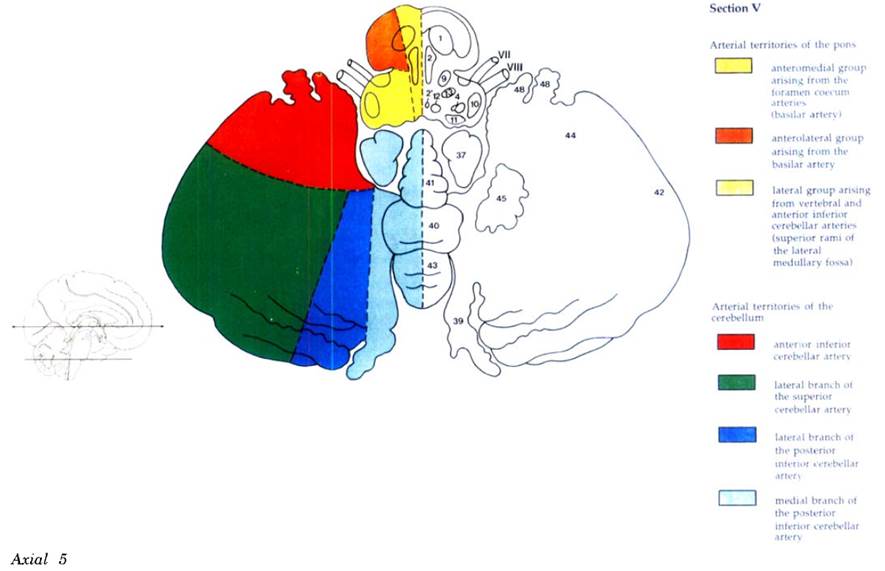

Cerebral vascular territories

Brainstem